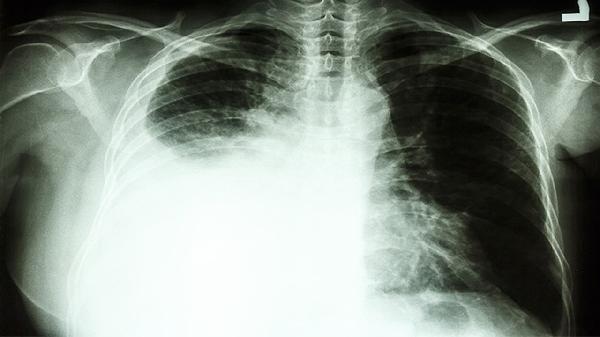

肺癌咳血的根本原因在于肿瘤组织侵犯或破坏了肺部血管,因此药物治疗仅为对症止血的环节之一,关键在于积极治疗肺癌本身。患者及家属切勿自行购买和使用止血药,错误的用药可能延误病情或引发不良反应。一旦出现咳血,应立即就医,由肿瘤科或呼吸科医生进行全面评估。治疗可能包括针对肿瘤的放疗、化疗、靶向治疗或介入栓塞止血等综合方案。日常生活中,患者应保持安静,避免剧烈咳嗽和用力,采取侧卧位防止血液误吸入健侧肺,饮食宜温凉、细软,避免过热、粗糙及刺激性食物,严格戒烟并远离二手烟,遵医嘱定期复查,监测病情变化。